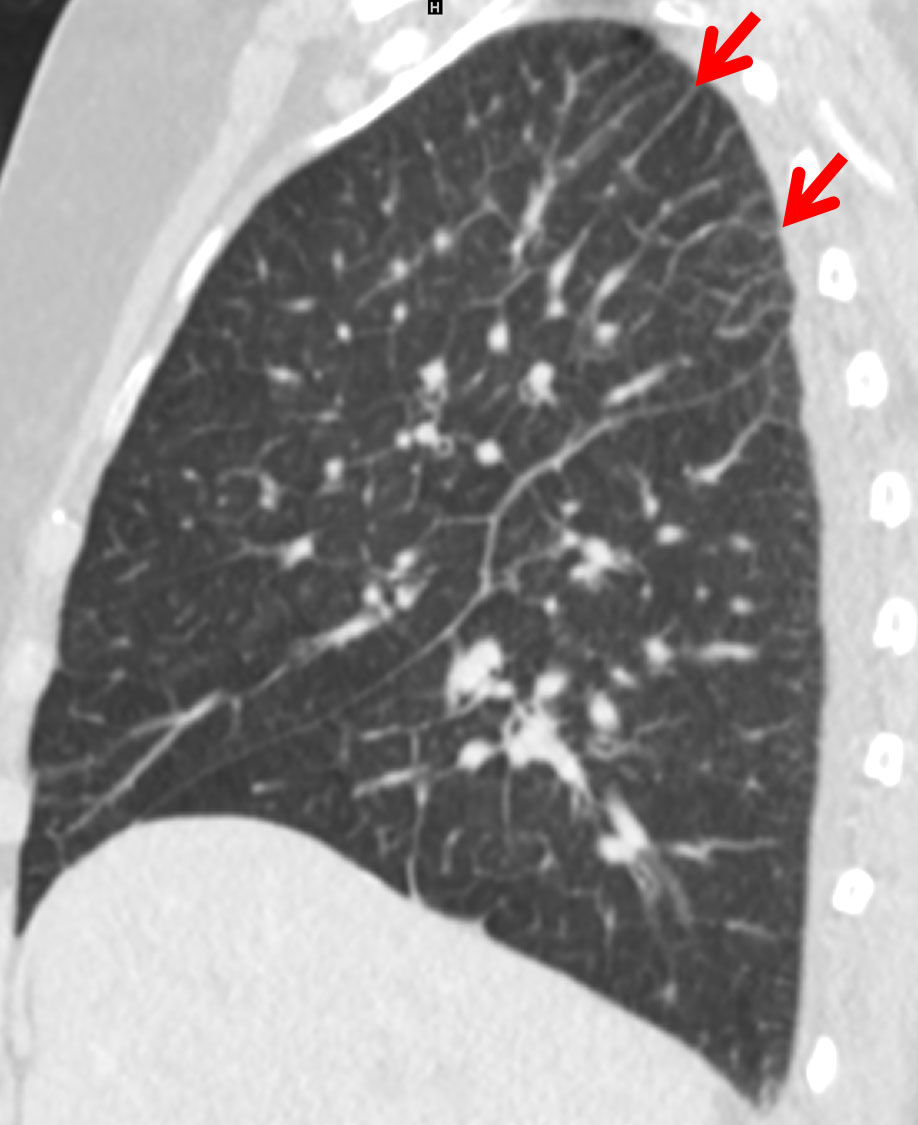

Interlobular septal thickening (IST) in the lung apex was present in of 81% and 76% of the cardiac and renal groups, respectively, which was significantly more than in the ILD group (26%, p <0.0001, figs 1–4 ). The distribution in the insufficiency group was more homogenous throughout the lungs than in the ILD group, in which the amount of septal thickening increased to 90% towards the lower lobes (table 2). The average thickness of the interlobular septa was rated between 1 and 2 with significantly thicker septal lines in the insufficiency group (1.45 ± 0.6) compared with the ILD group (1.28 ± 0.5; p <0.0001, fig. 3).

Figure 2 Predominantly apical Kerley B lines (red arrow) due to early pulmonary congestion in a 74-year-old male patient with cardiac insufficiency.

In this study, more than 80% of the patients with cardiac insufficiency and more than 70% of the patients with renal insufficiency presented with IST (Kerley B lines) in the lung apex. Miniati et al. described an identical distribution of the septal lines on conventional chest x-ray in the lower lungs among patients with heart or renal insufficiency [19]. While their distribution in the insufficiency group was homogenously throughout the lungs, the amount of Kerley B lines in our study increased to 90% towards the lower lobes in the ILD group. Findings of ILD predominate in the lung bases [8]. Patients with heart or renal insufficiency showed peribronchial cuffing due to increased capillary hydrostatic pressure or decreased oncotic pressure [1, 20]. One reason for the apical prevalence of the Kerley B lines in congested patients could be the redistribution of the pulmonary blood flow into the cranial parts of the lung, probably increasing the capillary pressure with resultant transudation. Kerley B lines are not a new sign in chest radiology, but their location in the lung apex is here described for the first time.